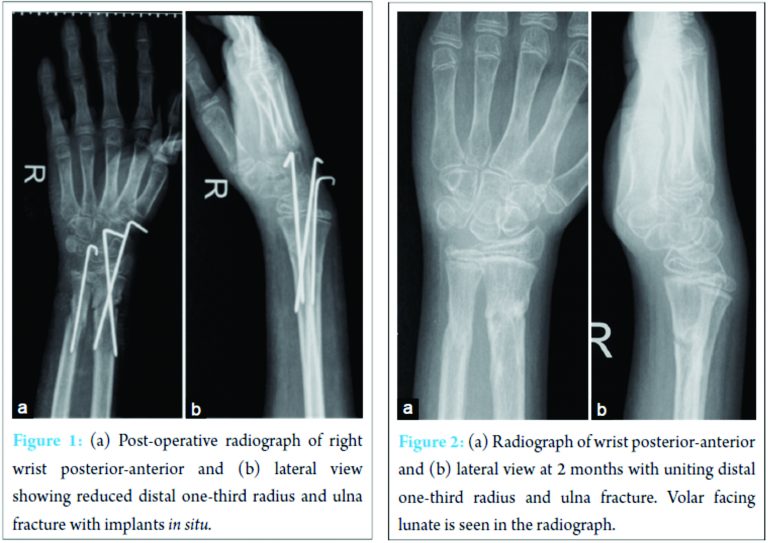

13‑year‑boy had sustained distal one‑third radius and ulna fracture after fall on an outstretched hand. Open reduction and K‑wire fixation was performed for both bone fracture forearm (Fig. 1). Implants were removed after 4 weeks (Fig. 2).